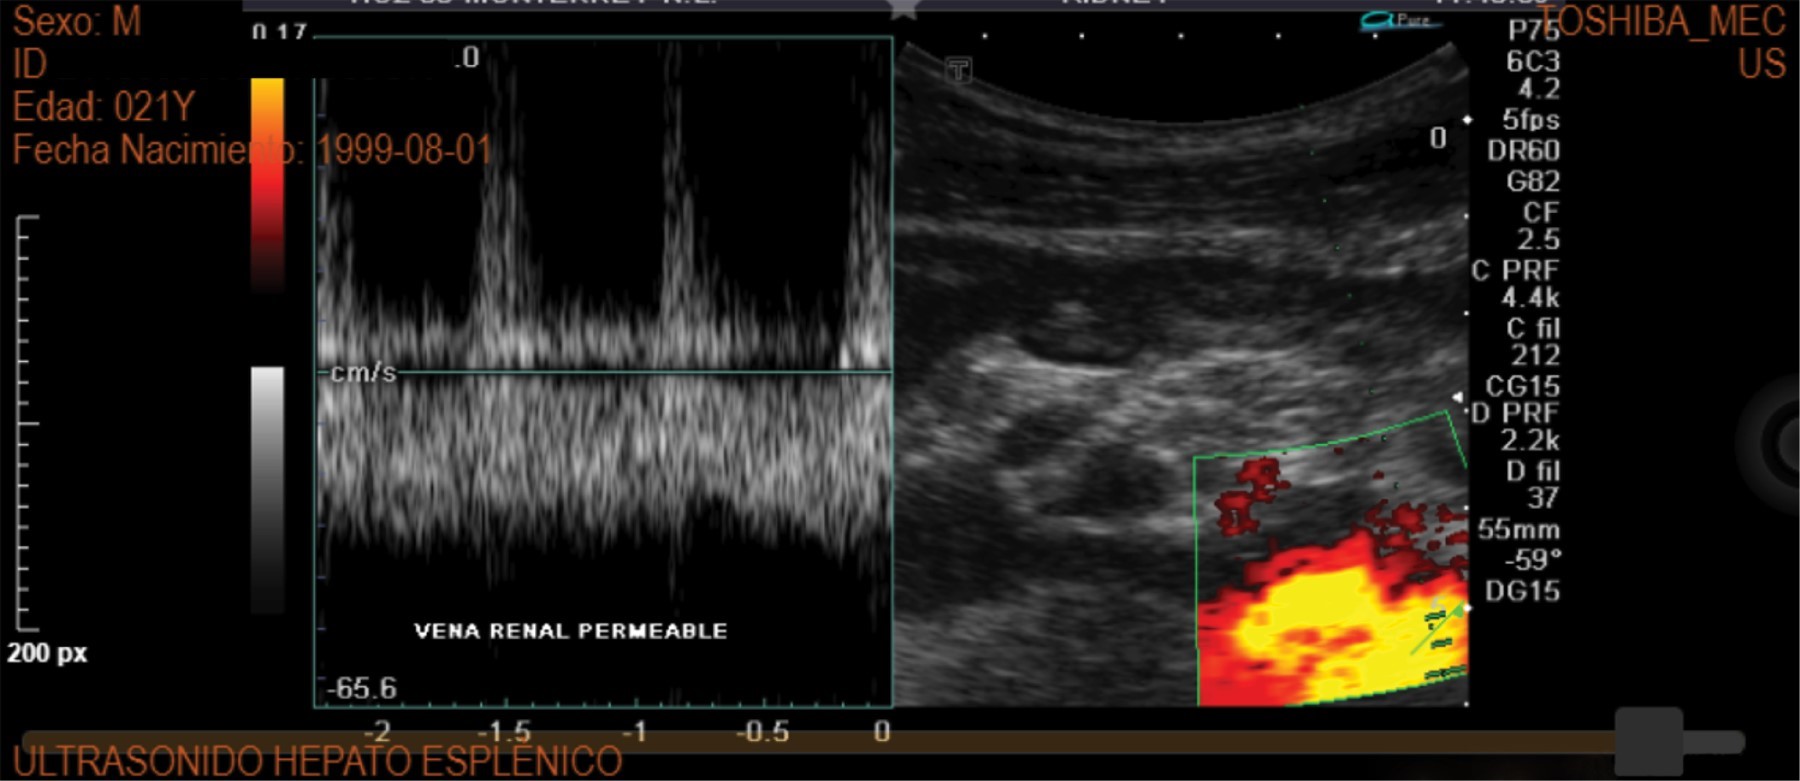

Figure 3